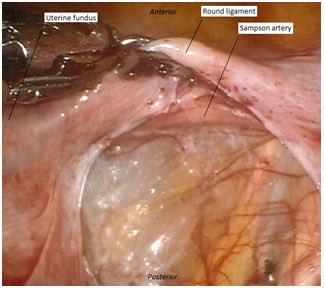

Sampson’s artery is located below the round ligament next to the uterus, and creates an anastomosis between the uterine and ovarian arteries. While physiologically insignificant, injury to this vessel can be a source of bleeding during surgery. 1/2